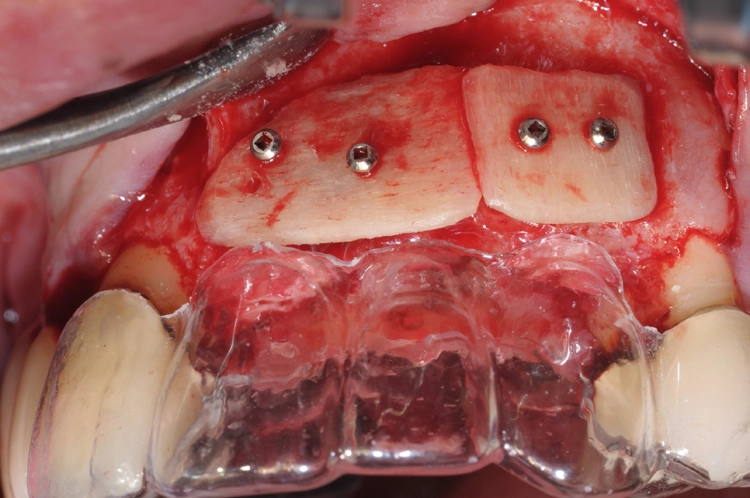

Die Abbildungen 11 und 12 dokumentieren das augmentative Relining, das zum Schutz vor Resorption und zur Konturaugmentation dienen soll. Dabei wurde eine Schicht bovines Knochenersatzmaterial (Straumann® XenoGraft) direkt auf den neu aufgebauten Knochen aufgetragen und mit Hilfe einer Kollagenmembran (Jason® membrane, Straumann) konturiert und vernäht. Damit legt man dem darunterliegenden neu aufgebauten Knochen einen Schutzpanzer an, der ihn einmal mehr vor Resorption schützt und die weitere Regeneration begünstigt.

Praxis Dr. Robert Würdinger

Diese Form der Überaugmentation gibt dem Behandler nicht nur eine Möglichkeit an die Hand, die Konturen noch einmal zu justieren. Darüber hinaus treten erfahrungsgemäß im Rahmen der Implantatfreilegung auch weniger Weichgewebedefizite auf, die dann später durch entsprechende Transplantate wieder ausgeglichen werden müssten. Gerade im Frontzahnbereich ist eine möglichst große Volumenstabilität für das ästhetische Ergebnis von großer Bedeutung.